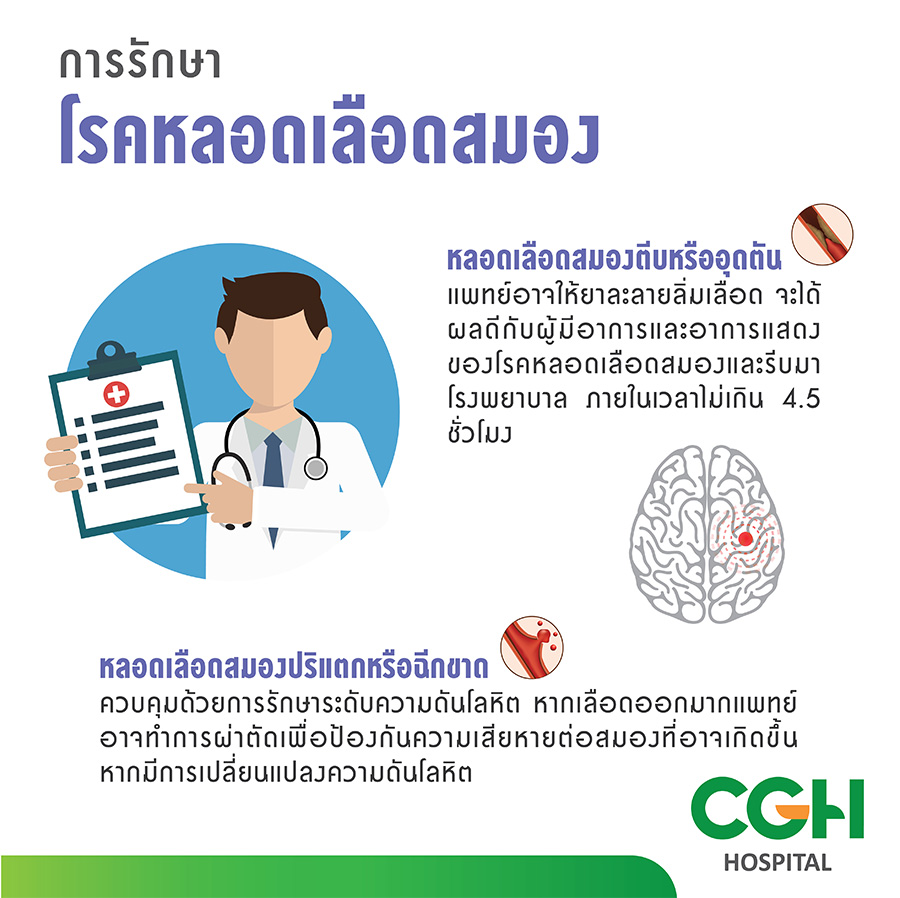

ระยะหลอดเลือด จังหวะหัวใจ Thrombus โจมตีระบบไหลเวียนโลหิตเวกเตอร์อินโฟ … 99,600+ ระบบหายใจ ระบบไหลเวียนโลหิต ภาพประกอบ ภาพถ่ายสต็อก รูปภาพ และ …

โรคหลอดเลือดสมอง | โรงพยาบาลซีจีเอช 95,300+ ลำตัว ภาพประกอบ ภาพถ่ายสต็อก รูปภาพ และภาพปลอดค่าลิขสิทธิ์ – iStock